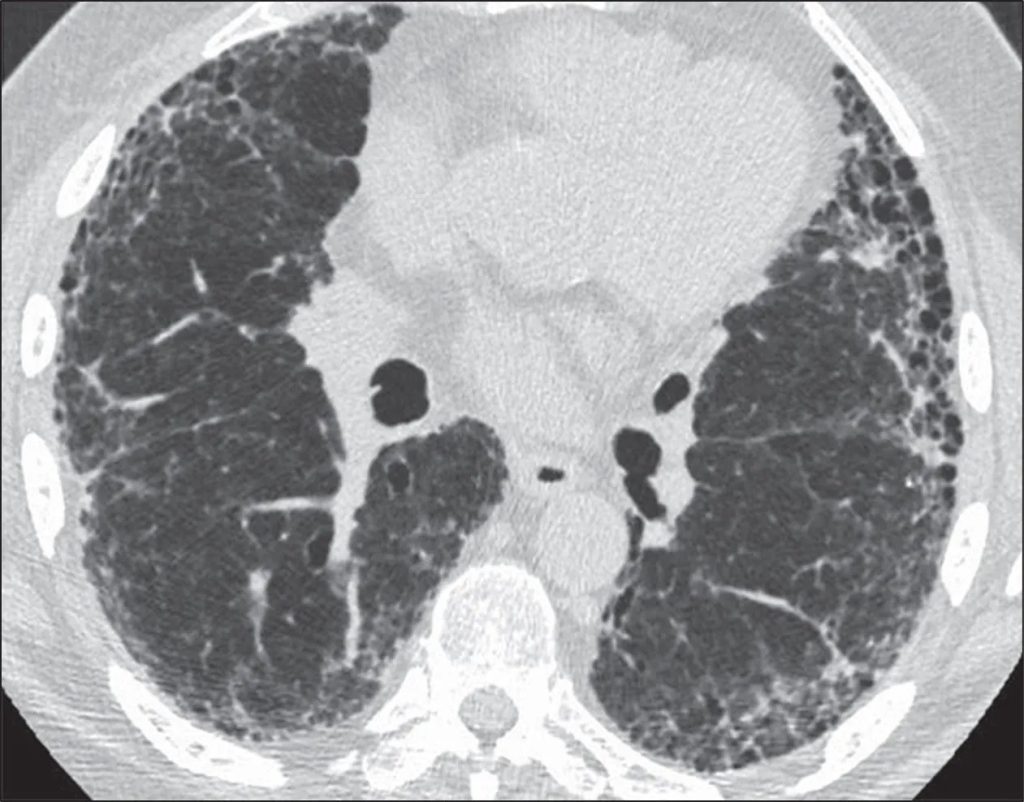

Η ακτινογραφία θώρακος και κυρίως, η αξονική τομογραφία θώρακος δείχνουν επίταση του δικτύου με συρρέοντα ινωτικά στοιχεία, περιβρογχικές παχύνσεις του διάμεσου ιστού και βρογχεκτασίες εξ έλξεως με κατανομή από τα μέσα και προς τα άνω πνευμονικά πεδία, κυρίως, ενώ οι βάσεις προσβάλλονται ελάχιστα. Εστίες θαμβής υάλου αναπτύσσονται ανάμεσα στις περιοχές ίνωσης και συρρέουν προς τα μέσα πνευμονικά πεδία σε μεγαλύτερη έκταση. Επίσης, υπάρχουν οζίδια στις ίδιες θέσεις. Οι πύλες των πνευμόνων δε συμμετέχουν και δεν υπάρχει εικόνα μελικηρύθρας.

Η απάντηση του BAL/Bronchoalveolar lavage/Βρογχοκυψελιδικό έκπλυμα σε συνδυασμό με την προσβολή των άνω και μέσων πνευμονικών πεδίων, το μωσαϊκό πρότυπο και τα στοιχεία ίνωσης δείχνουν χρονιότητα.